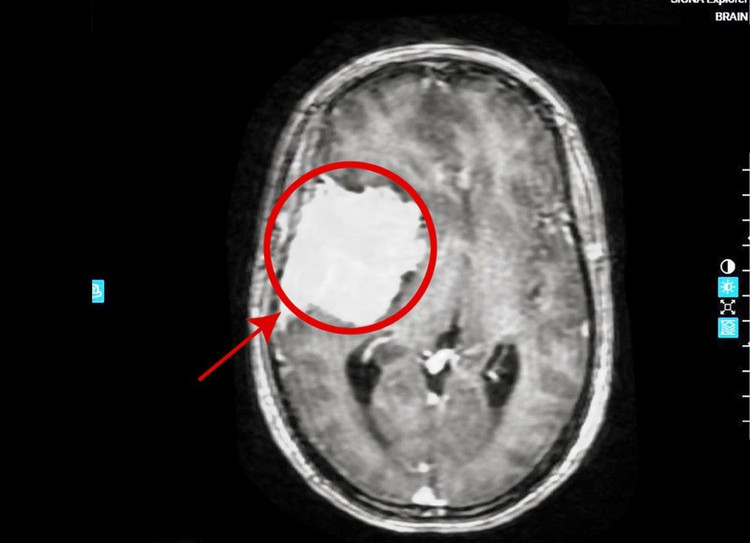

Chị Trang (45 tuổi) đau đầu kéo dài nhiều ngày tưởng do tiền đình nên chủ quan không đi khám. Gần đây triệu chứng đau đầu tiến triển nặng kèm méo miệng, suy giảm ý thức… Người bệnh tới Bệnh viện Đa khoa Tâm Anh khám phát hiện khối u não kích thước 5x7 cm ăn mòn xương sọ, đẩy lệch đường giữa não.

Khối u khổng lồ trong não người bệnh - Ảnh BVCC

TS.BS Nguyễn Đức Anh, Trưởng khoa Ngoại Thần kinh Cột sống, Bệnh viện Đa khoa Tâm Anh Hà Nội chỉ định người bệnh chụp MRI phát hiện khối u não: Kích thước 5x7 cm; Ăn mòn xương sọ, đè đẩy sâu vào cấu trúc não; Làm lệch đường giữa tới 10mm sang bên đối diện.

Người bệnh cần phải nhập viện điều trị ngay. Nếu để muộn, người bệnh có nguy cơ thoát vị não, ảnh hưởng đến trung tâm tuần hoàn và hô hấp trong não gây các di chứng thần kinh không hồi phục hoặc thậm chí tử vong bất kỳ lúc nào.